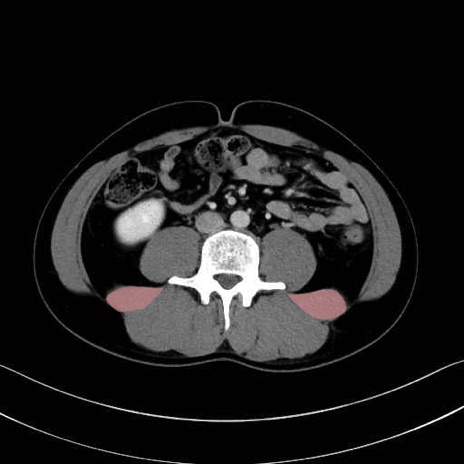

腰方形筋 (Quadratus lumborum)

大腰筋 (Psoas major)